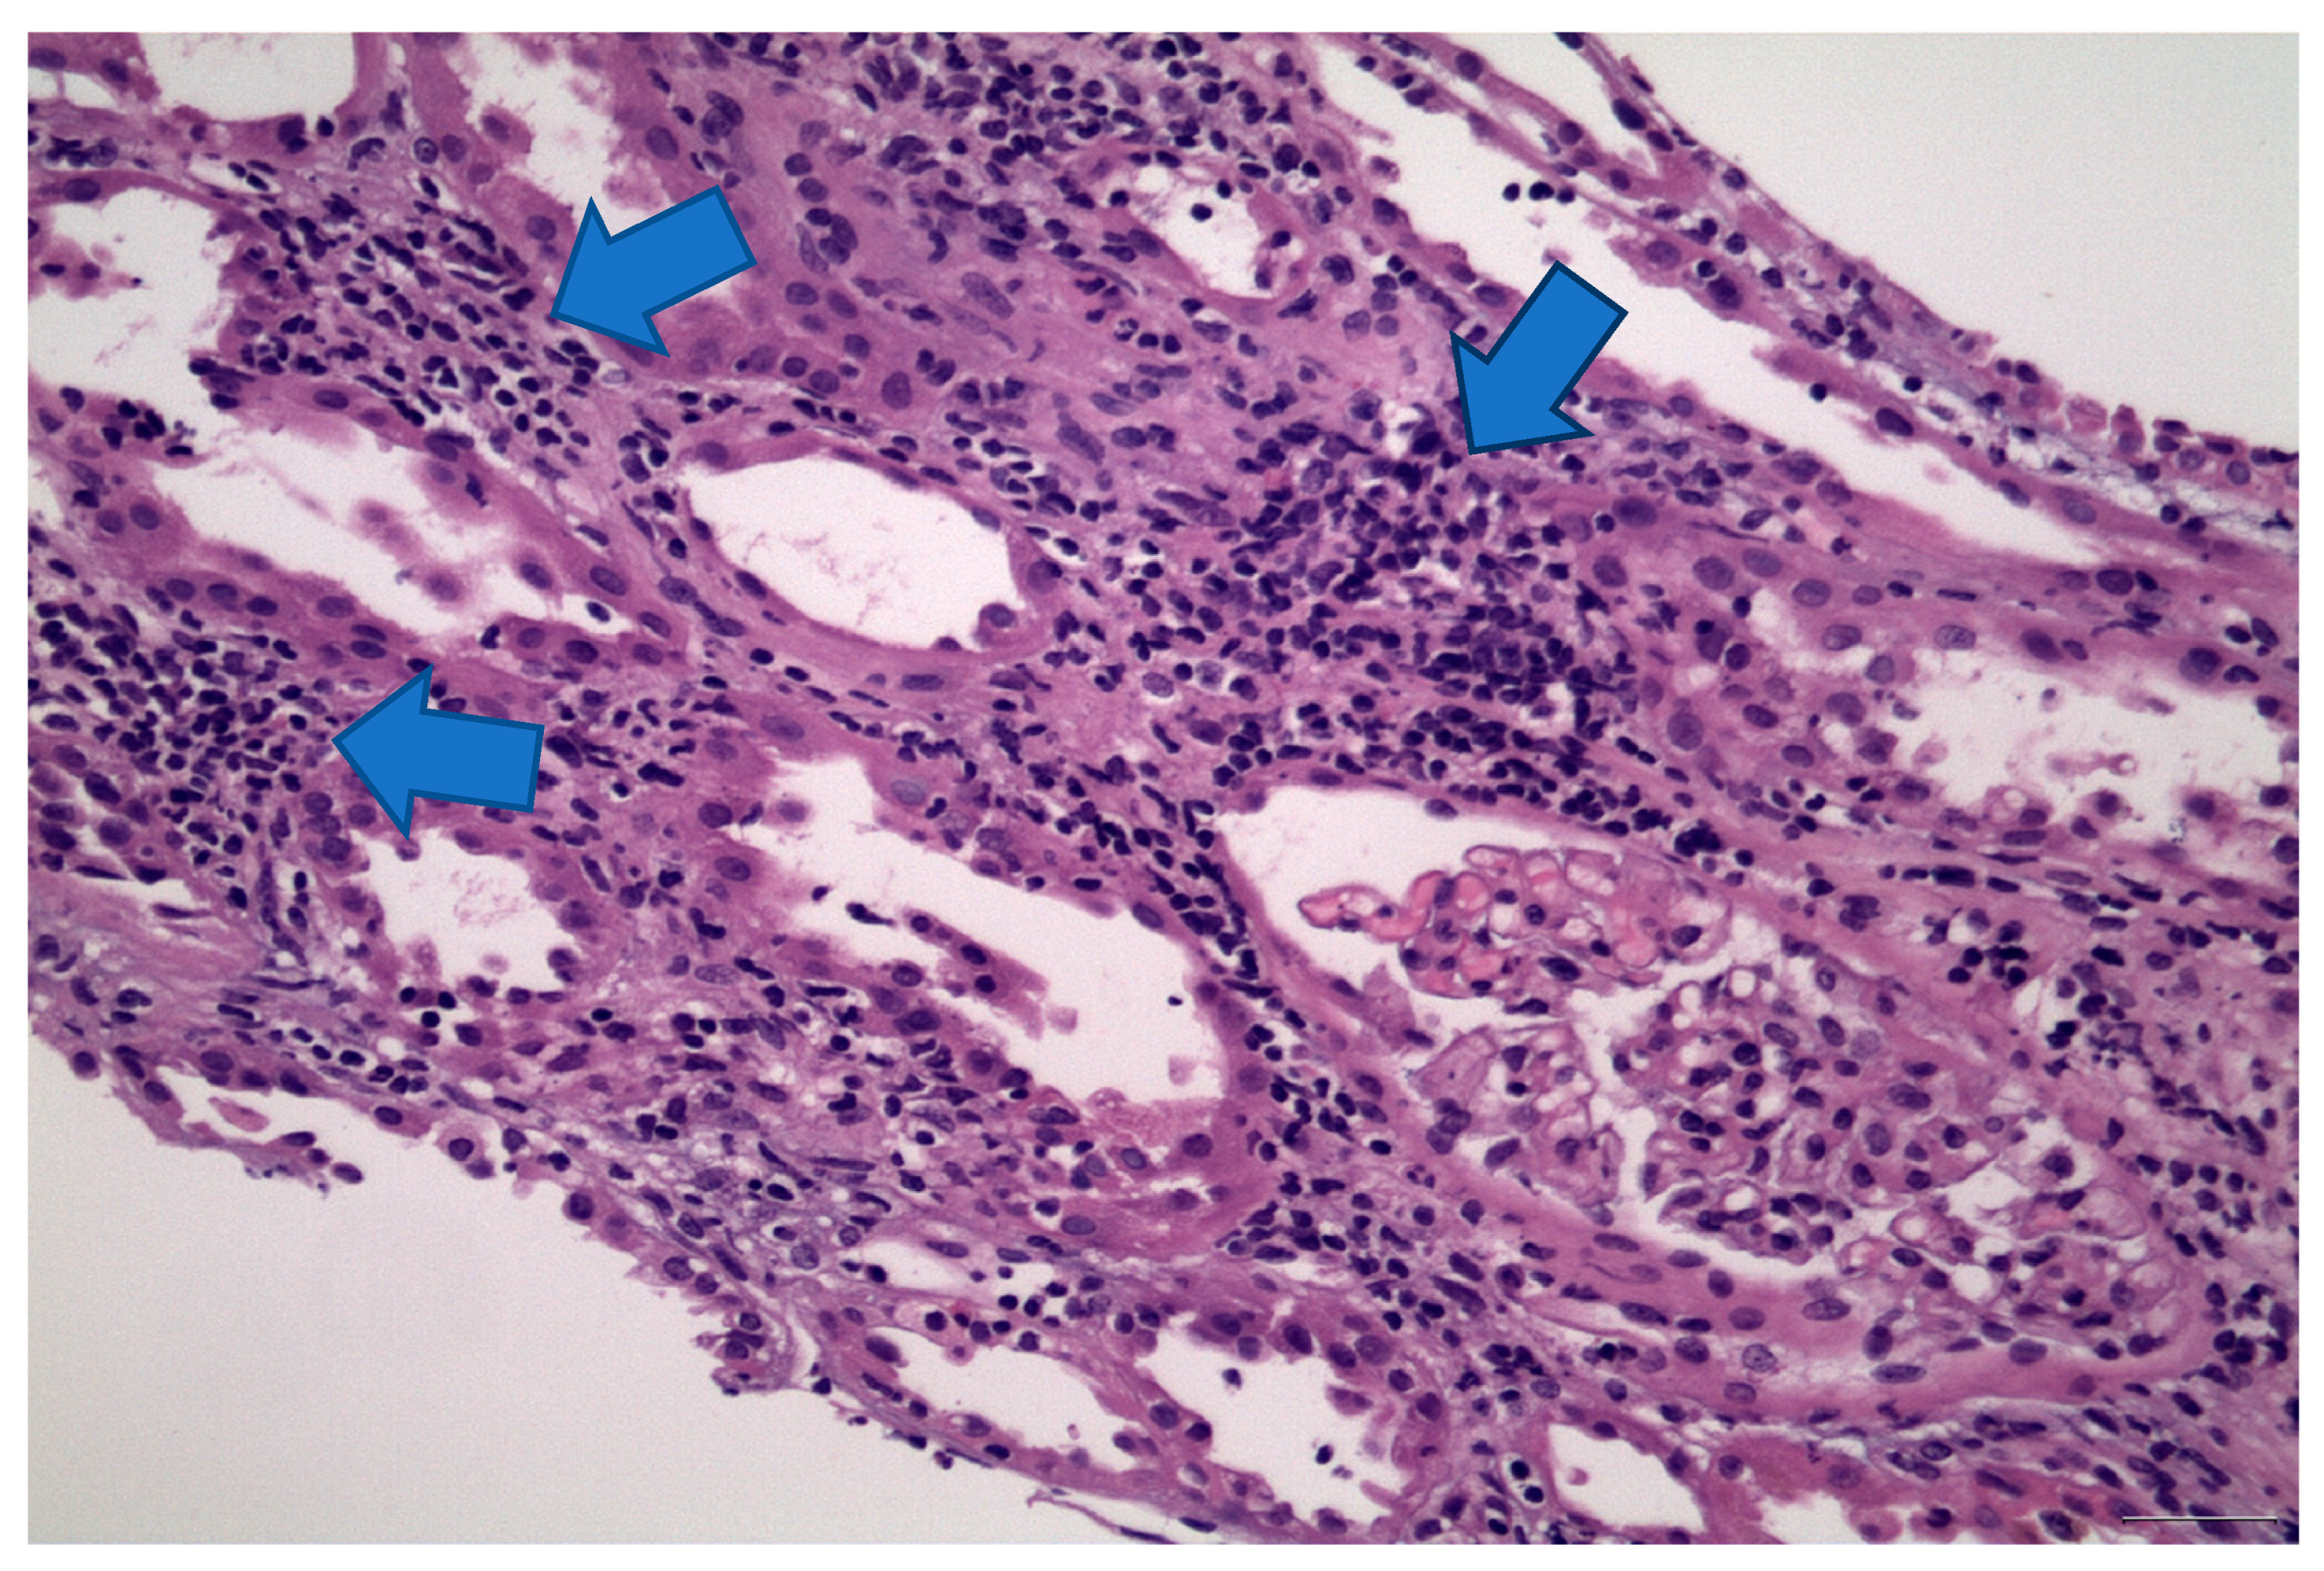

2. Case 1 Description: MCD Associated with Tamoxifen